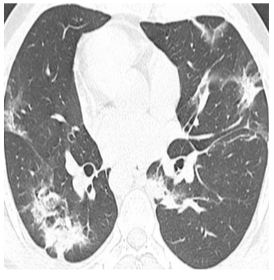

Unlike recent works, we aim to answer the question: “how can we boost the performance of COVID-19 diagnosis algorithms by exploiting other source knowledge relevant to a radiologist’s decision?”. Specifically, given a baseline network, we expect to improve its accuracy by incorporating properly two important knowledge sources: an infected and a heat-map region without modifying its architecture. In our settings, infected regions refer to positions of Pulmonary Consolidation Region (PCR) (as shown in figure 1 at the middle, green regions), a type of lung tissue filling with liquid instead of air; and Ground-Glass Opacity (GGO), an area of increased attenuation in the lung on CT images with preserved bronchial and vascular markings (as depicted in figure 1 at the middle, red regions). By quantifying those regions, the radiologists can distinguish normal and infected COVID-19 tissues. While infected areas are based on medical knowledge, we refer to heat-map (as shown in figure 1 at the right-hand side) as a region extracted from a trained network, which allows us to understand transparently essential parts in the image directly impact the network decision. Our method motivates from the two following ideas. Firstly, we would like to simulate how a radiologist can comprehensively consider both global, local information, and their prior knowledge to make final judgments by associating global images, infected regions, and heat-maps during the training process. Secondly, for avoiding network suffering by a significant level of noise outside the lesion area, an attention mechanism to supervise the network is necessarily such that it can take both lesion regions and global visual information into account for a final decision.

We then extracted a maximum connected region in and mapped with the original CT scan to get our local branch’s final input. One can see a typical example of the heat-map area in figure 1 on the right-hand side. Given this output and coupling with an infected model obtaining from algorithm 1, we now have enough input to start training the proposed model.